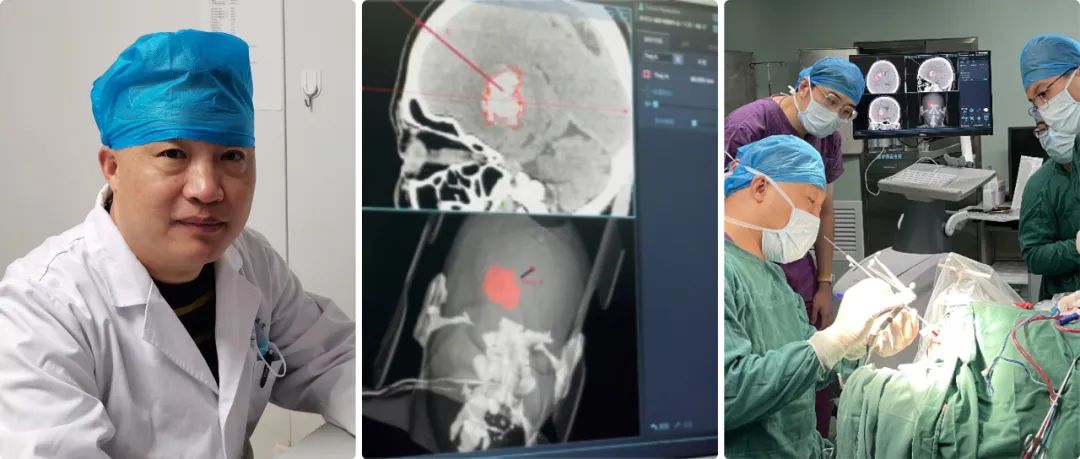

但是大部分病人雖然是腦出血,但是病人生命體征比較穩(wěn)定,我們盡可能用神經(jīng)導航來實現(xiàn)微創(chuàng)血腫穿刺引流。

神經(jīng)導航微創(chuàng)手術就避免了傳統(tǒng)開顱手術的弊端,它可以實現(xiàn)精準穿刺血腫引流,病人一次性接受手術,恢復比較快,并對病人整體創(chuàng)傷很小。

高磊:準備做神經(jīng)導航手術之前,我們給患者進行顱腦CT薄層掃描,層厚大約在0.625毫米-1毫米,然后在神經(jīng)導航系統(tǒng)進行重建,在重建虛擬像上選擇合適的靶點。

靶點選擇的三個原則:第一,從頭皮到血腫的穿刺路徑比較短;第二,避開大腦重要功能區(qū);第三避開重要的神經(jīng)血管。

我們經(jīng)過對病人注冊,實現(xiàn)在電腦上與實際人頭部位置融合,再根據(jù)電腦上確定的穿刺位置,選擇實際病人顱上的穿刺位置,兩者基本上重合,這樣確保穿刺路徑的精準性。

高磊:任何手術設備,尤其導航系統(tǒng),漂移不可避免;Sinovation神經(jīng)導系統(tǒng)的誤差可以控制在0.5毫米左右。

我們對腦組織等漂移怎么克服呢?第一精準定位,第二實時導航,就是穿刺點確定后,我們通過顱骨鉆孔到達皮層,再進行一次注冊和校正偏差,確保漂移減到最小的程度。

高磊:目前兩人操作,真正進行手術一人就可以,另一位在臺下操作電腦、注冊系統(tǒng)等;隨著技術越來越成熟,如果大家對這種手術都熟悉了,一人操作也可以完成。

高磊:目前我們的導航系統(tǒng)已經(jīng)應用了大約半年時間,使用的效果和大家的反響都不錯;導航系統(tǒng),一旦熟悉之后操作比較簡單。

自從引進導航系統(tǒng),我們科室技術水平得到了大幅的提升,正如剛才所講沒有導航之前,我們腦出血都是手術開顱,徒手穿刺誤差比較大,穿刺效果也比較差,有時病人的病程住院時間延長了,而且效果也不好。

現(xiàn)在我們有了導航,穿刺技術可以說得到了質(zhì)的飛躍;在導航輔助下,基本上可以說穿刺百發(fā)百中,病人術后恢復也非常快,功能改善也非常顯著,科室技術水平得到了飛躍式的提升,區(qū)域及周邊病人的社會評價也反響很好。